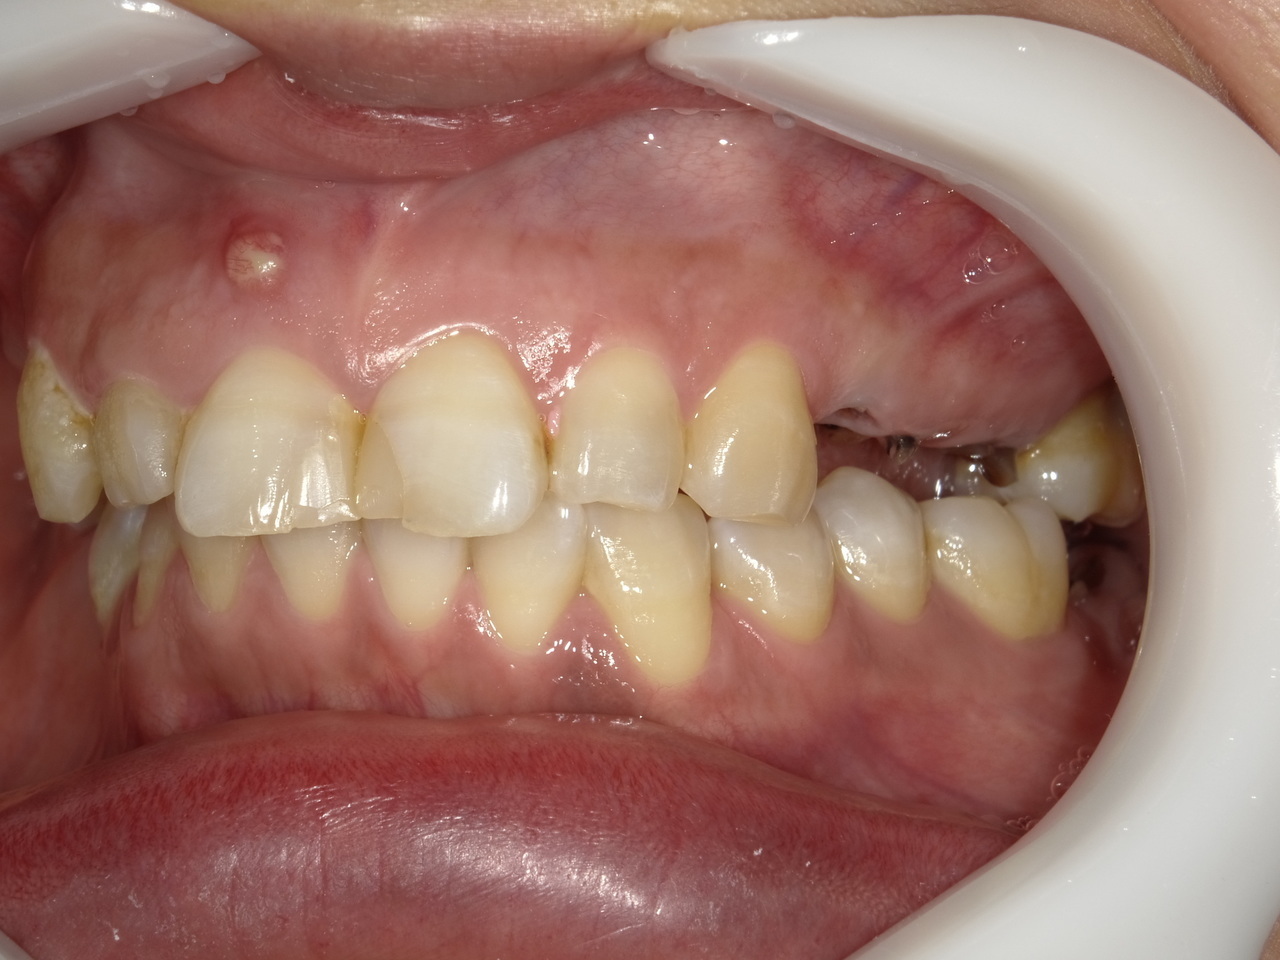

3.左上5の頬・舌側の大幅な骨欠損と上顎既存骨3mmまでの骨欠損がおこった症例に対しておこなったインプラント治療

After

枚方市のインプラントの症例

I・K 様 女性 40代

症状としては、左上5の歯根破折を起こしていたため、排膿と自発痛をみとめた。それにともなう骨の大きな欠損。

治療法としては、炎症が強くたったためと、炎症による頬側側歯肉の退縮を認めていたために、まず、抜歯を行い上顎洞内及び歯抜した周囲組織の回復を試みた。その後、患者様がインプラント治療を希望したため、薄い上顎骨に対しては、グラフトレスサイナスリフト、骨欠損部には、人口骨補填を行い、頬側歯肉が退縮していることを改善するために、1回法でリーリングアバットメントを装着して、アバットメントの上に歯肉が覆うようにして、歯肉のボリューム回復を行った。2か月後、インプラントが骨と結合していることを確認して、光学印象を行い、2週間後にアバットメントとジルコニアクラウンを装着した。

治療結果としては、大幅な骨欠損があったが、グラフトレスサイナスリフトと骨欠損部に人工骨を補填して、抜歯した穴が自然に治る状態にしたことで、2か月半という短い期間での治療を完了することができた。(仮に、GBRや通常のサイナスリフトでの治療を行っていたら、最低でも1年は、かかってくる治療であると考える。)また、今回は、即時荷重を避け、1回法での治療を行ったことで、噛めない期間ができてしまったが、1回法で行ったことにより、歯肉のボリュームが増して、ブラッシングがしやすい口腔内環境にすることができた。低侵襲で、短時間で、治療を終えることができ、また、審美性・機能性の回復も行えたことができた。

治療の期間・回数:約2.5か月、6回

治療の価格:368,500円(税込)

治療費の内訳:インプラント基本料(フィックスチャー及び手術費用、投薬費用、レントゲン費用、インプラント上部費用(アバットメントおよびジルコニアクラウンの費用用)330000円(税込み)。オプション費用グラフトレスサイナスリフト費用プラス人工骨費用 38500円(税込み

治療のリスクや副作用:手術後に、痛みや腫れ、出血、合併症などを引き起こす可能性があります。噛む感覚がご自身の歯と異なる場合があります。見た目がご自身の歯と異なる場合があります。手術後にメインテナンスを継続しないと、インプラントが抜け落ちる可能性があります。